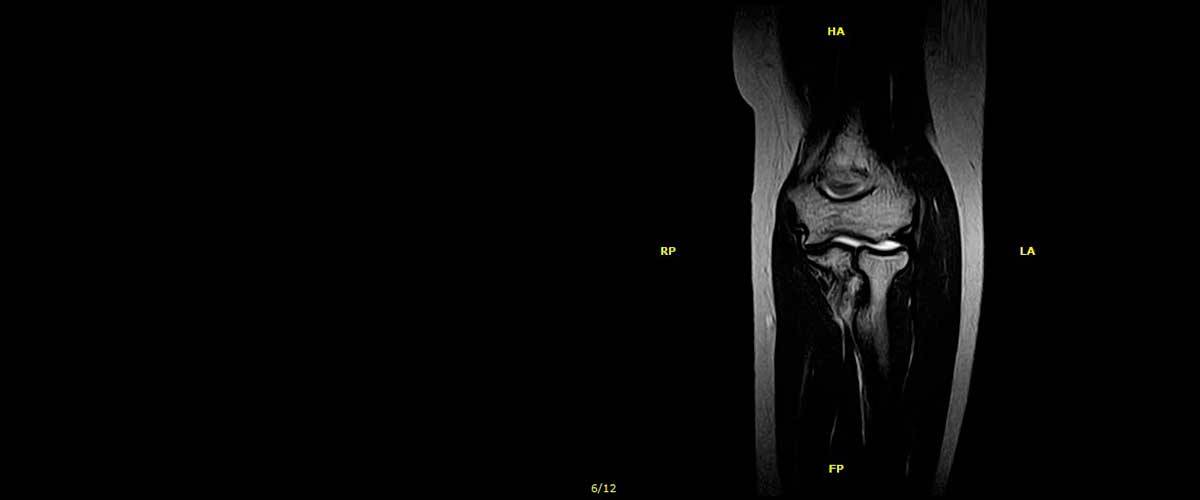

Contamos con equipos de resonancia magnética musculo-esquelética capaces de realizar exámenes con descarga de peso o bipedestación.

En nuestros centros se realizan estudios y diagnósticos de resonancia magnética musculo-esquelética

de Resonancia ,Magnética Musculo-Esquelética, de la marca italiana Esaote, es único en su diseño ya que nos permite realizar exámenes en bipedestación (el paciente estará de pie, para que se tenga otra perspectiva del comportamiento del cuerpo durante el examen).